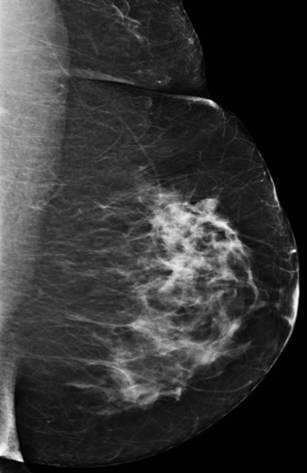

Ung thư vú

» Thông tin: Nữ giới – 58 tuổi.

» Lâm sàng: Khối tuyến vú.